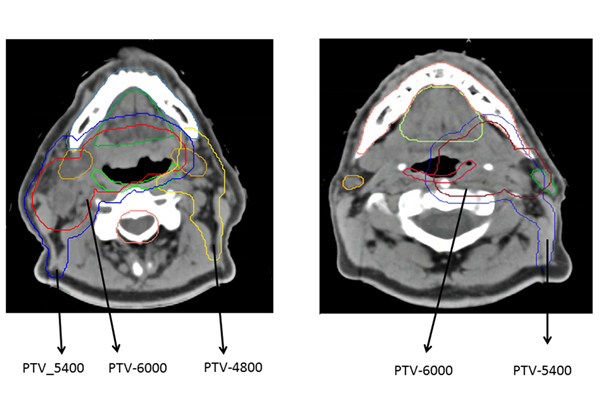

Five bench mark patients, who were treated on a previous clinical trial of HPV-associated oropharyngeal cancer patients, RTOG 1016 and who met the more selective inclusion criteria for NRG HN002, were identified for this study. There was diversity among the cases with respect to the primary site within the oropharynx (tonsil or base of tongue), primary tumor stage (T stage), and nodal stage (N stage). The contours of the target volumes and organ at risk were redrawn according to the guidelines of NRG HN002. Figure 1 gives examples of axial views of two CT images included in this study and showing planning target volume (PVT) and organs at risk (OARs).

Figure 1 Examples of axial views of two CT images included in this study, showing PTVs and OARs.